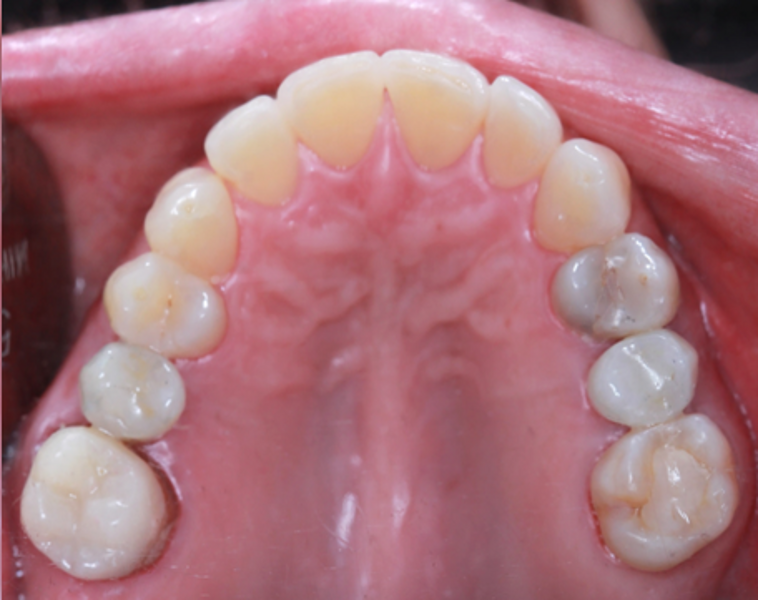

Initial situation

A 38-year-old female patient presented to the dental office reporting social discomfort when smiling, owing to the absence of both maxillary second premolars (Figs. 1a– c, Figs. 2a–c & 3). Clinical examination revealed that tooth #16 had an intra-radicular post and had been prepared for a crown, but the crown was missing, and a cavity was noted on the distal surface of tooth #14. Overall, the patient exhibited a healthy periodontal condition. She was a non-smoker and did not present with any comorbidities or systemic health issues. CBCT imaging showed adequate bone quality and quantity at both sites and no signs of acute infection. Additionally, a residual root was identified at site #15 beneath the already healed gingiva.

Fig. 3: Occlusal view of the initial situation.